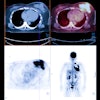

FAPI-PET shows promise in patients with lung cancer

April 15, 2024